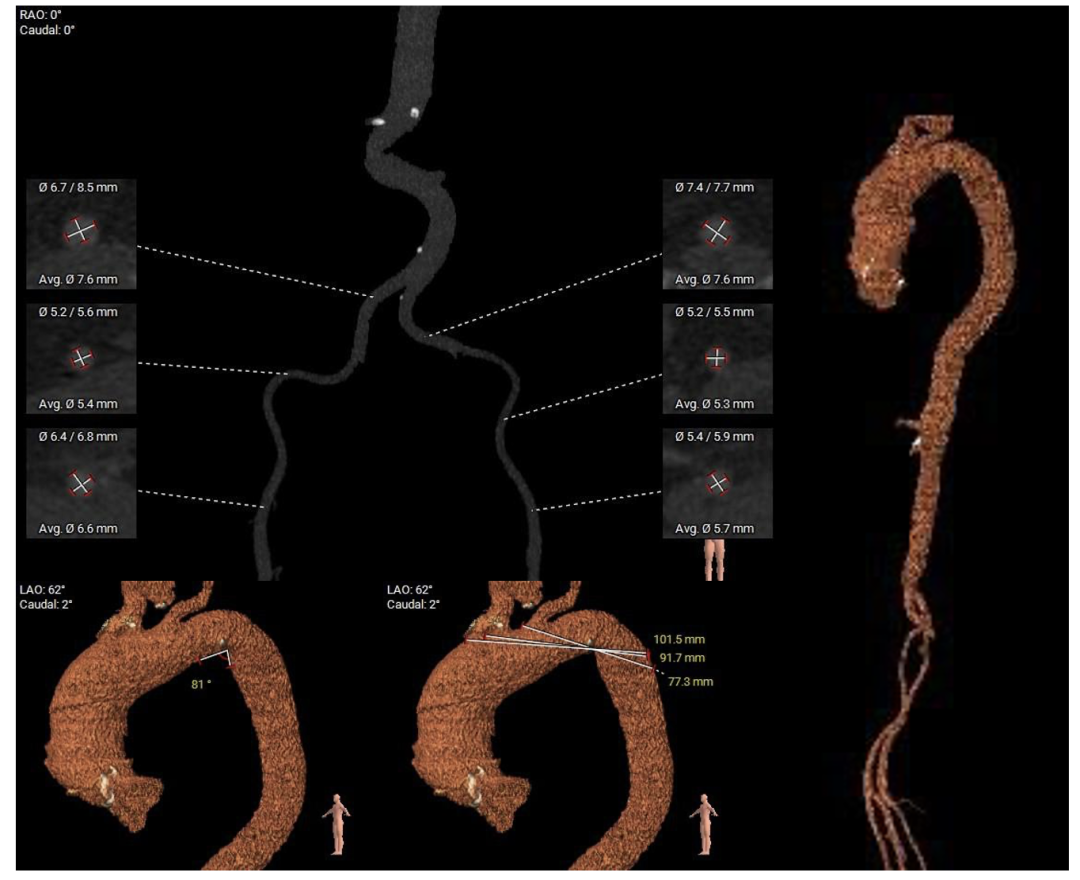

在完成术前CT扫描后发现,李阿姨入路腹主动脉严重扭曲、横位心、右冠窦无冠窦钙化融合且冠脉开口位置相对较低,左冠瓣叶冗长,术中冠脉闭塞风险高,这些不利因素均会明显增加手术的难度和风险。为此,医院迅速启动多学科协作机制,由医务处牵头,联合心血管科、麻醉科、重症医学科、血管外科、胸外科等专家团队展开会诊。经过反复讨论,专家团队最终决定采用国际先进的治疗方案一一经导管主动脉瓣置换术(TAVR)。这种微创手术无需开胸,只需通过血管穿刺即可完成瓣膜置换,极大降低了手术风险。为确保万无一失,心血管科团队还通过线上会议邀请国内知名专家对病例进行远程讨论,制定了精细化手术方案,包括入路解决方案、冠脉保护策略、术中应急措施以及术后康复计划。

▲主动脉弓及外周入路测量

2. 腹主入路折角:双侧入路血管走形良好,整体入路血管条件一般,腹主动脉可见扭曲,经过测量33cm可以正好通过迂曲部位,也提前备好45cm长鞘,以防血管损伤。